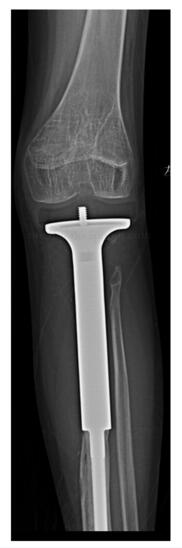

图47‐8 术后5年X 线左胫骨上段

图47‐9 术后5年X 线左胫骨上段侧位

:患者术后未见明显并发症。目前患者术后5年,未发现局部复发及远隔转移。患者跛行步态。左膝关节主动活动度(伸直至屈曲):0~90°。下肢长度测量显示左胫骨较右胫骨短缩4.4cm,左股骨较右股骨短缩约3.1cm(图47‐7)。X 线显示假体未见明显松动,膝关节无脱位(图47‐8~图47‐10)。患者站立时由骨盆及脊柱倾斜来调整肢体长度(图47‐11)。

图47‐10 术后5年X 线显示假体未见明显松动,膝关节位置无脱位a﹒正位片;b﹒侧位片